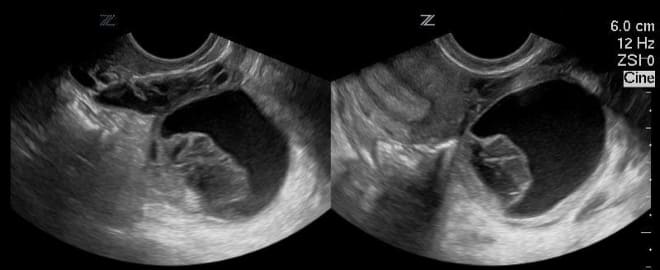

Главным признаком кисты яичника при ультразвуковом исследовании является образование полого отростка на его поверхности. В отличие от нормального фолликула, который изменяется в течение менструального цикла, киста остается неизменной. Кроме того, такое образование обычно имеет больший размер.

На ультразвуковом снимке киста яичника отображается в виде черного пятна, размеры которого варьируются от 3 до 20 см.